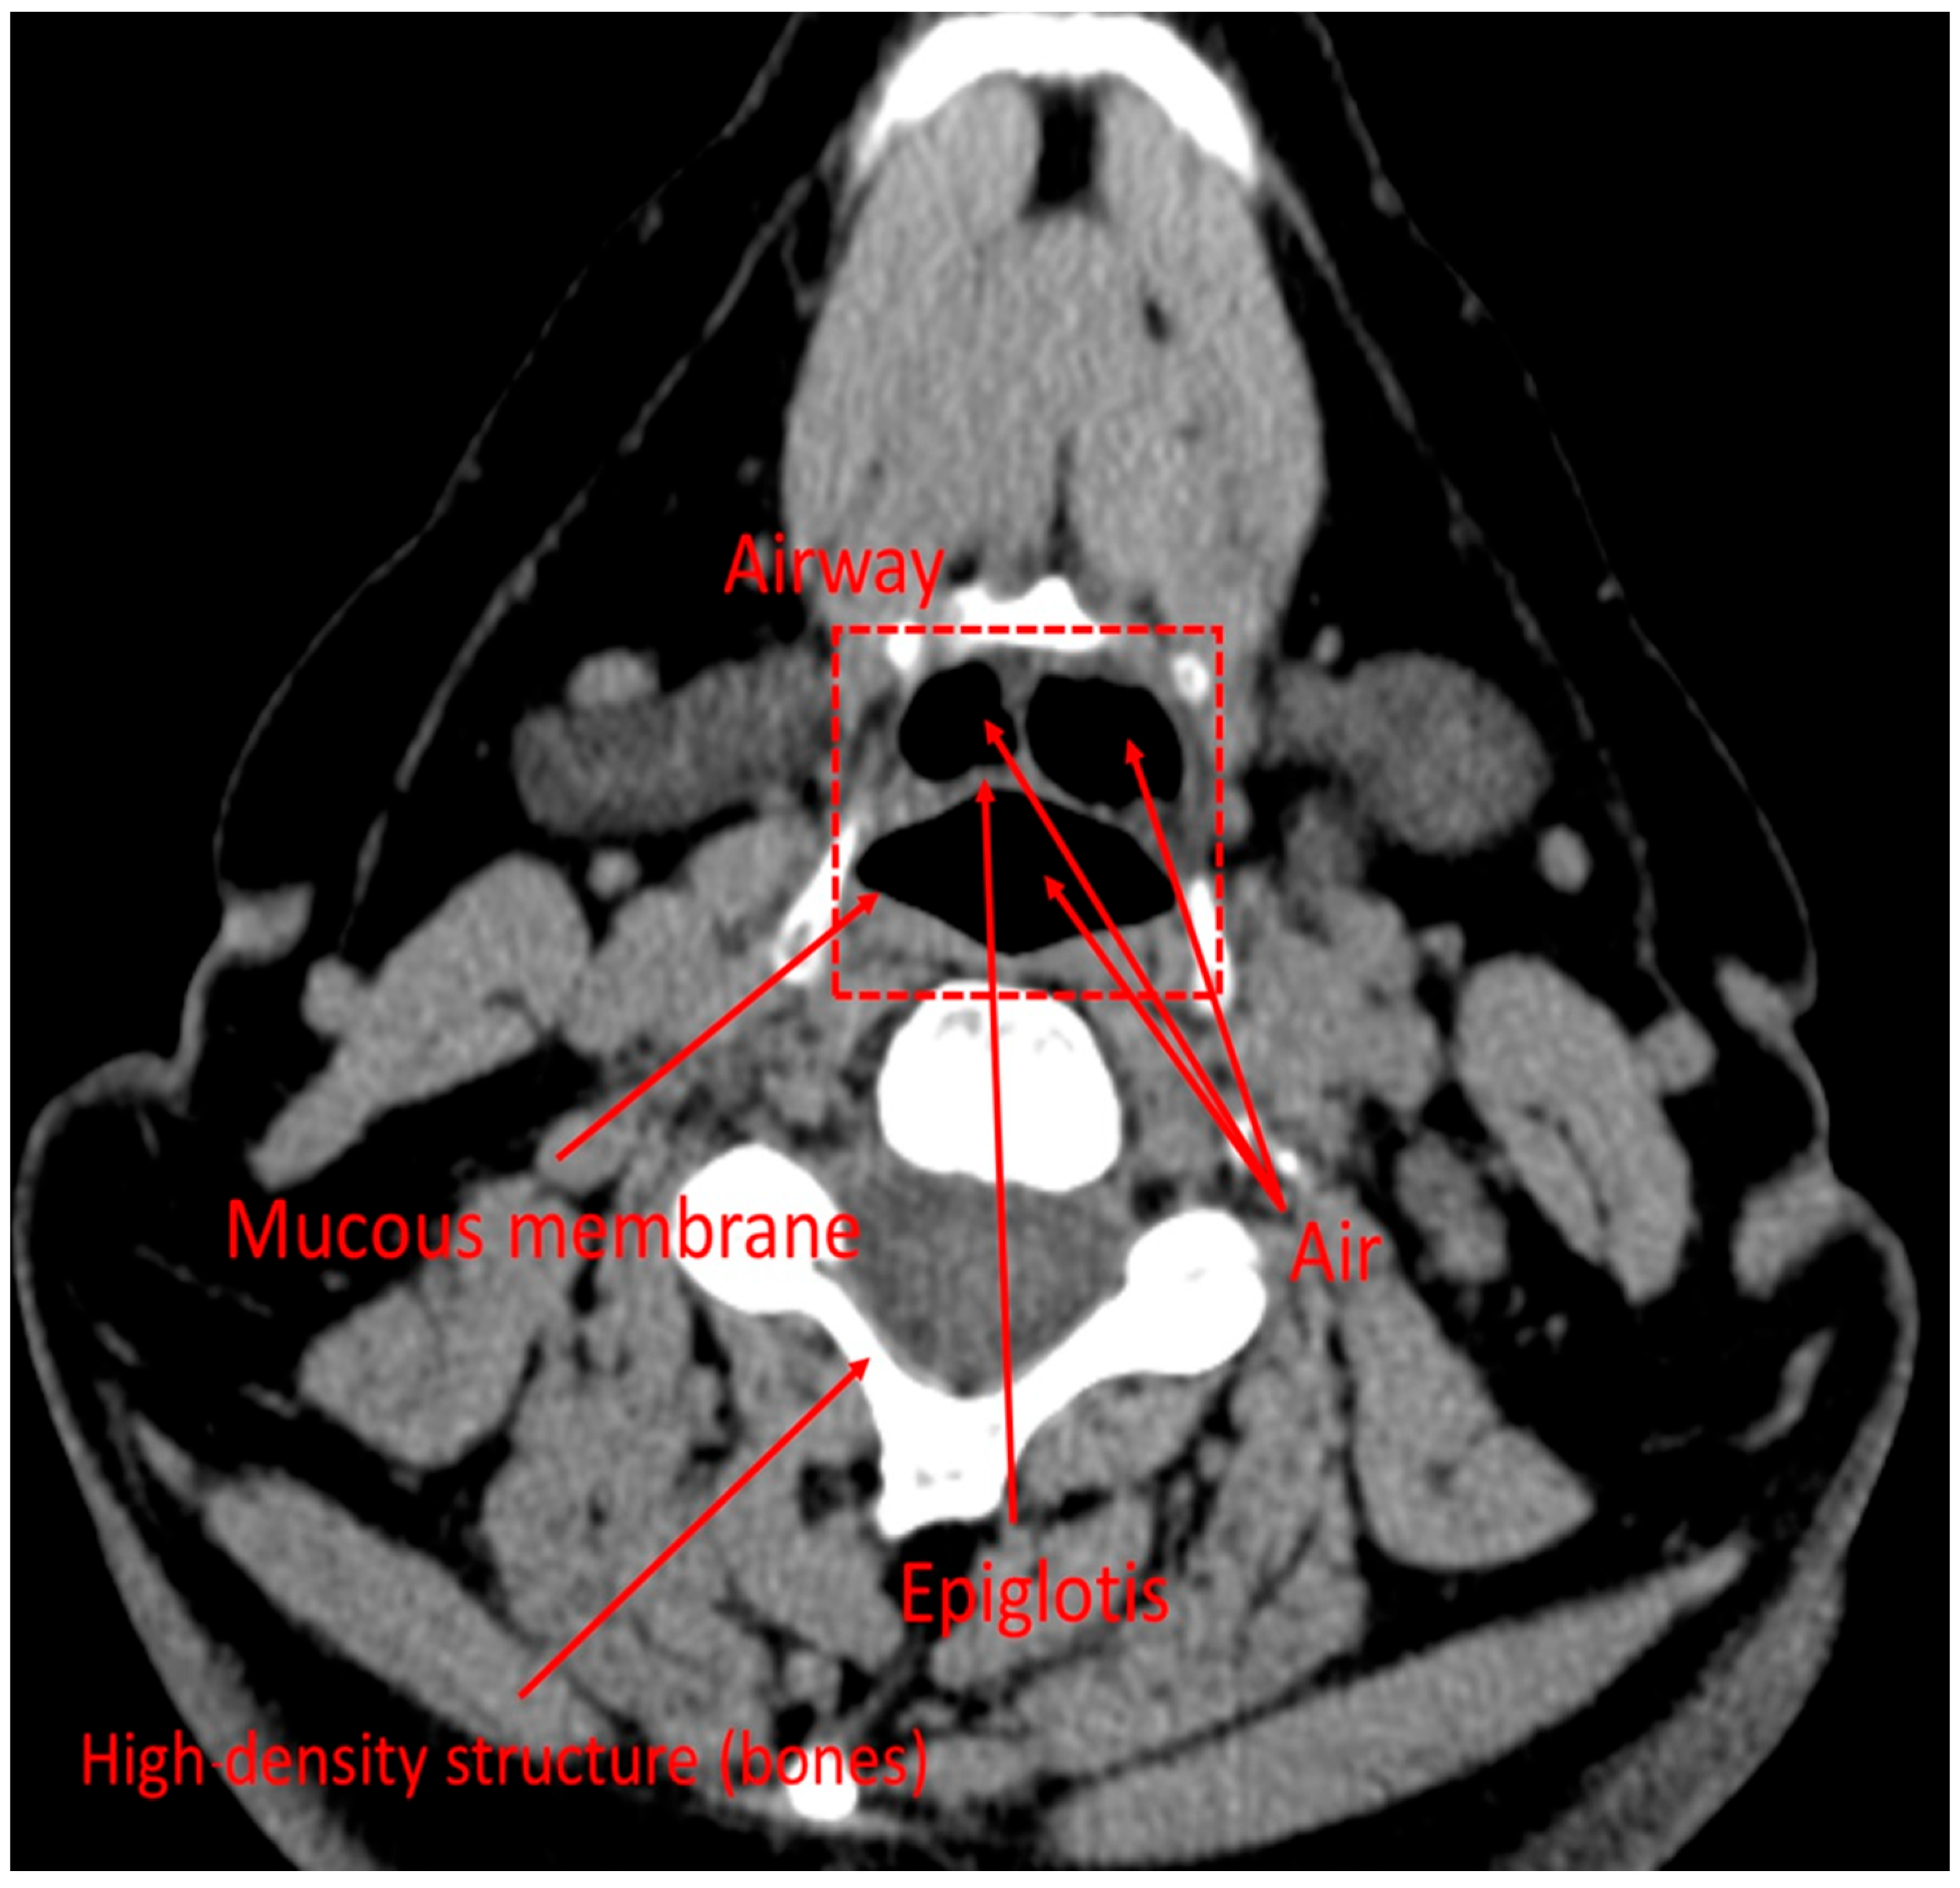

First, an anonymized CT scan captures cross-sectional images, stored in DICOM format, containing both imaging data and patient metadata. RadiAnt DICOM viewer was used to analyze image properties, including pixel dimensions. Airways appear dark on CT images due to the low X-ray attenuation of air, whereas soft tissues appear in shades of gray and bone appears white (Figure 3). To isolate airways, Fiji software (version 2.16.0) was employed. The air–mucous membrane boundary, seen as a transition between dark air-filled spaces and grayish soft tissue, was identified using the threshold function. Unwanted gaps were filled using the Flood fill function, ensuring that only airway structures remained present.

Figure 3. CT image of the supraglottic region in the axial plane.